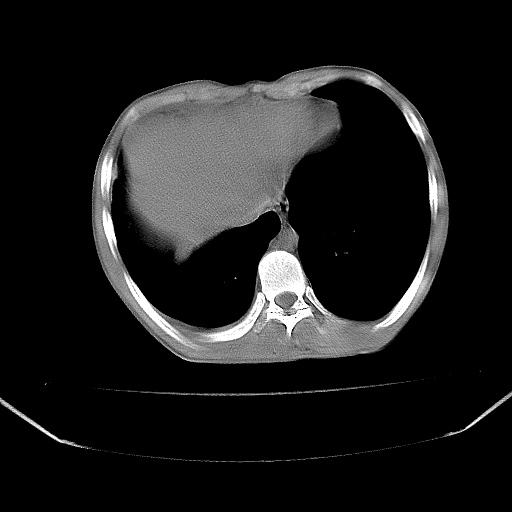

以下是引用zjzjr在2008-7-20 12:57:00的发言:[br]考虑为生殖源性肿瘤(内胚窦瘤),侵袭性胸腺瘤可能性大;右侧少量胸腔积液。

以下是引用xinliheng001在2008-7-20 21:17:00的发言:[br]右纵隔巨大分叶状软组织均质密度肿块,右上肺叶受压明显,纵隔右移、胸膜受累有少量积液和结节样增厚。应增强扫描一定会有更具诊断价值的信息。

以下是引用xinliheng001在2008-7-20 21:17:00的发言:[br]右纵隔巨大分叶状软组织均质密度肿块,右上肺叶受压明显,纵隔右移、胸膜受累有少量积液和结节样增厚。应增强扫描一定会有更具诊断价值的信息。